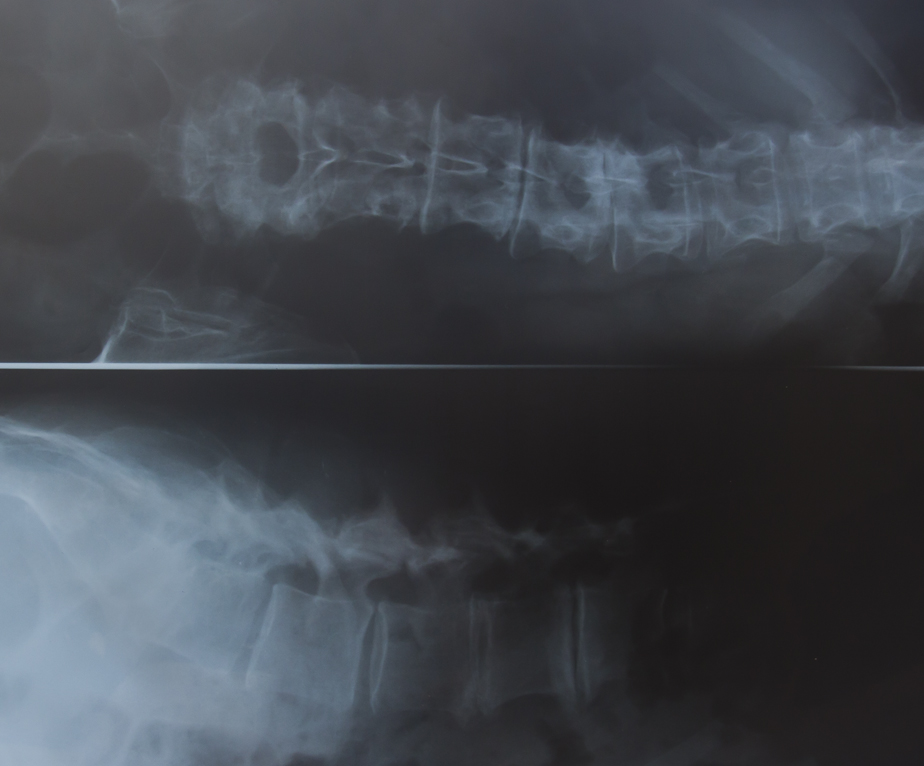

When a patient presents with acute low back pain (LBP), any red flag warnings of serious disease should first be excluded. Yellow and blue flag warnings of psychological factors should be noted. A psychological opinion of patients with substantial psychological distress could be sought. Advice may be offered on the benign nature of non-specific LBP. The person should be encouraged to be physically active and to continue with normal activities as far as possible. A structured exercise programme, that includes aerobic activity, movement instruction, muscle strengthening, postural control and stretching, should be devised. A combined exercise and psychological treatment programme that includes a cognitive behavioural approach can be considered in patients with significant disability or substantial psychological distress. A course of acupuncture may also be added. Manual therapy, including spinal manipulation, could be considered. Paracetamol should be the first medication option. If this is inadequate, a nonsteroidal anti-inflammatory drug or weak opioid, or both, can be added. Individual risks for side-effects and the patient’s preference should be taken into account. Strong opioids should be considered in patients in severe pain, but for short-term use only. Antidepressants and gabapentine or pregabolin can be considered when there is a neurogenic component of the pain. Consider obtaining a surgical opinion on patients who have completed an optimal package of care and who still have persistent severe non-specific LBP. Progressive neurological fallout requires a surgical opinion.